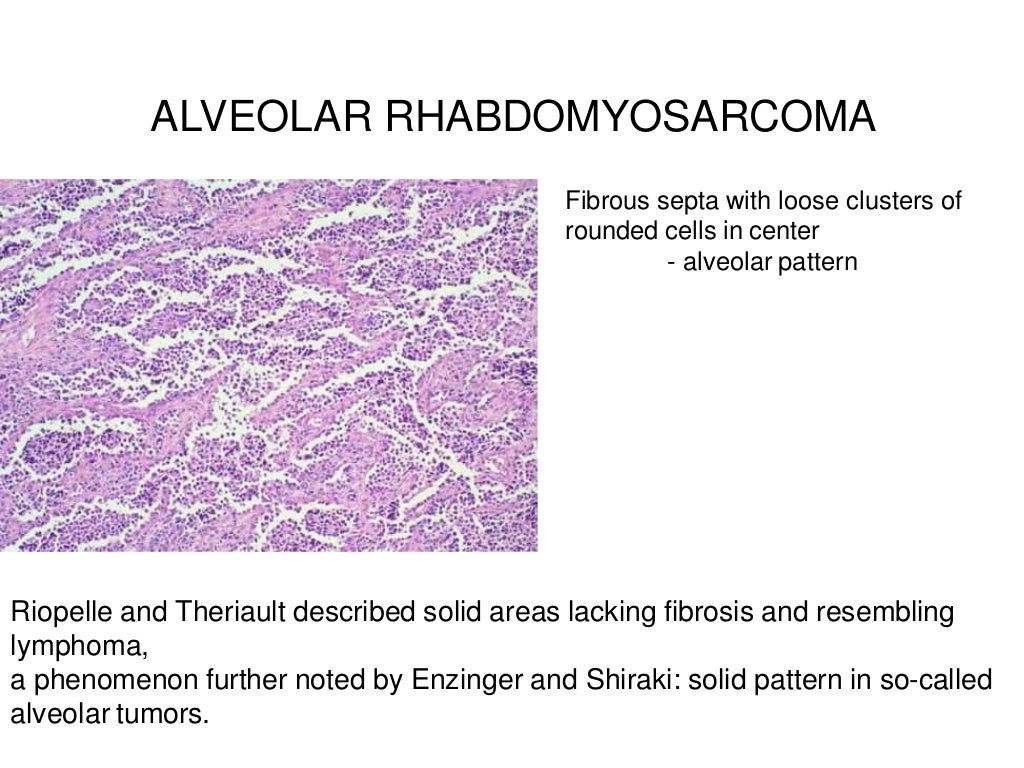

Rhabdomyosarcoma

www.slideshare.net

www.slideshare.net

rhabdomyosarcoma alveolar

Webpathology.com: A Collection Of Surgical Pathology Images

www.webpathology.com

www.webpathology.com

rhabdomyosarcoma alveolar webpathology pathology comments microscopic

Rhabdomyosarcoma mri tissue sarcomas. Mesothelial cells ascites,mesothelial cells in ascitic fluid,reactive. Rhabdomyosarcoma alveolar webpathology pathology comments microscopic